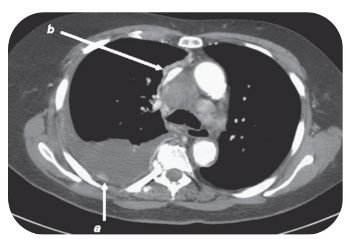

16

Q

A

Espessamento da pleura mediastinal sugere fortemente

derrame neoplásico.